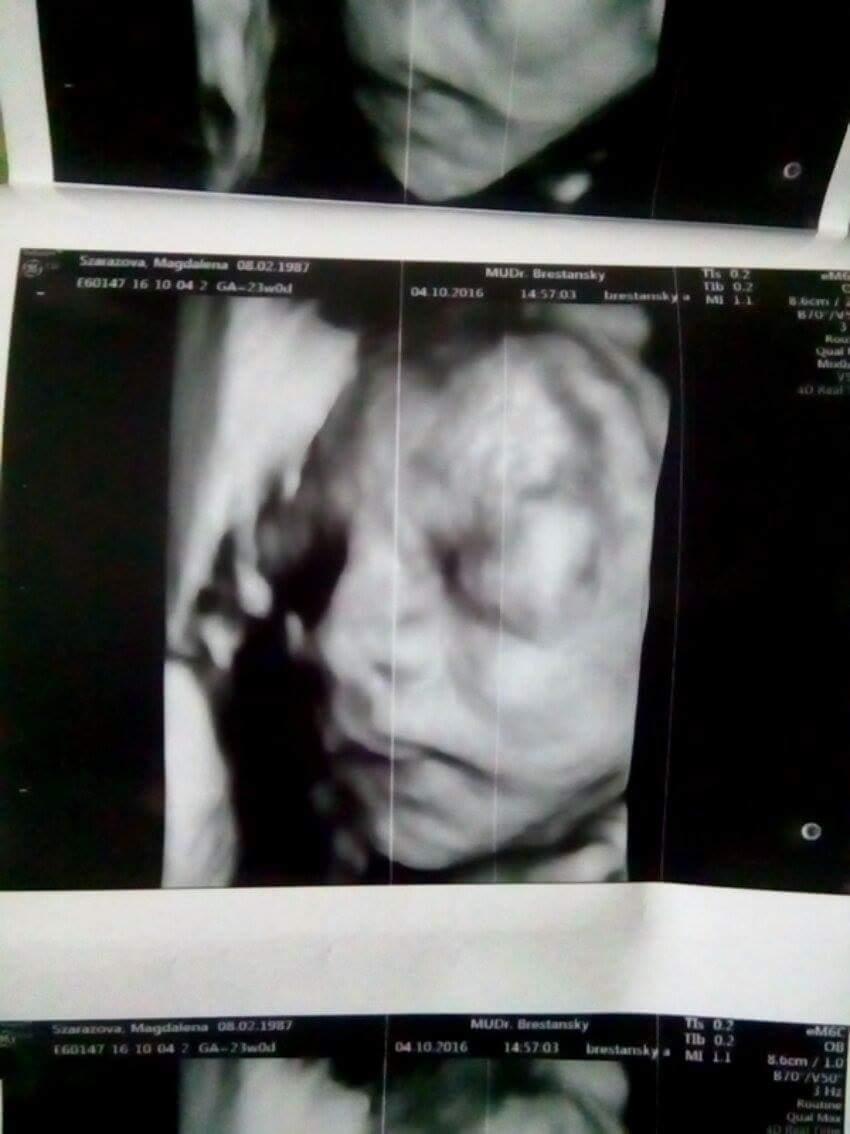

@zuzuk22 ja mam taku kazdu poradnu... nic mi nekontroluje, ani srdiecko, len sa opyta spoza stola, ci mam nejake problemy, naposledy som mu spominala nocne krce v nohach, tak mi predpisal magnezko a keby som nesla na 3d, co bolo pod jednym spojene s morfo ultrazvukom, tak doteraz o svojom babatku neviem nic...

@zuzuk22 myslela som si, ze kazda poradna takto prebieha, aj mamka mi spominala, ze ultrazvuk sa robi len trikrat, tak som nepanikarila... ale teraz, zhodou okolnosti, ako som bola na 3d, tak mi ho robila ina doktorka a kedze sa nam nase babo nechcelo ukazat, tak mi napisala do spravy, ze v najblizsej poradni sa ma moj doktor pozriet na to, ci chlapcek ci dievcatko a o dva tri tyzdne skontrolovat placentu, kedze ju mam vraj nizsie ulozenu... tak som sa az zacudovala, kolko ultrazvukov a v akom kratkom case je mozne urobit... asi to naozaj zavisi od pristupu dr

Ja keby som vcera nesla na to 3D,tak nic neviem. Naposledy na sone doktor na mojom sone zaucal nejaku studentku a potom jej dovysvetloval ich odbornymi nazvami a zacal diktovat sestricke- co vzdy ked zacne diktovat tak uz to je ako fajront. A ja mu hovorim,ze no ale teraz by ste mohli aj mne nieco povedat. Vravim kde ma hlavicku,kolko cca vazi,pohlavie nevidite? No mala som dost,on ju zaucil na mojom bruchu a mne nemienil nic povedat.